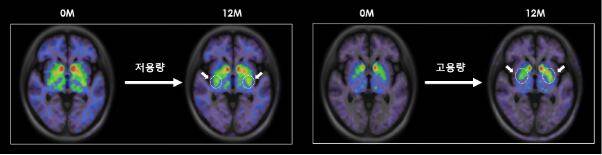

TED-A9 이식 1년 후 뇌영상 이미지 ([18F]FP-CIT PET)에서 투여 전 베이스라인 대비 도파민 수송체(DAT)의 발현이 증가되었음을 확인하였으며(그림 참조), 해당 뇌영상 결과 저용량군에 비해 고용량군에서 도파민 세포 생착 신호가 더 높게 측정되었다. 이러한 결과는 이식된 TED-A9이 뇌 속에서 생존하여 도파민 신경세포로 성숙되고 주변부와 시냅스를 형성하고 있다는 것을 시사하며, 사멸된 도파민 신경세포를 대체하는 파킨슨병의 근본적인 치료 메커니즘에 대한 강력한 증거라고 볼 수 있다.